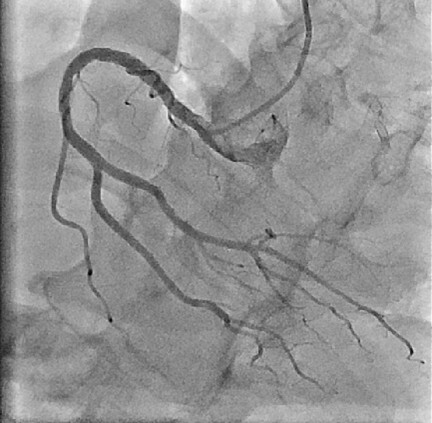

- 心臓カテーテル検査:手首や足の付け根に局所麻酔を行い、カテーテルという細いチューブを動脈の中に挿入し、透視下に冠動脈を直接造影する検査です。病気の程度を正確に診断し、適切な治療法を決定するのに有用な検査です。入院して検査を行います。所要時間は30分程度です。

(写真は心臓カテーテル検査によって得られた画像)